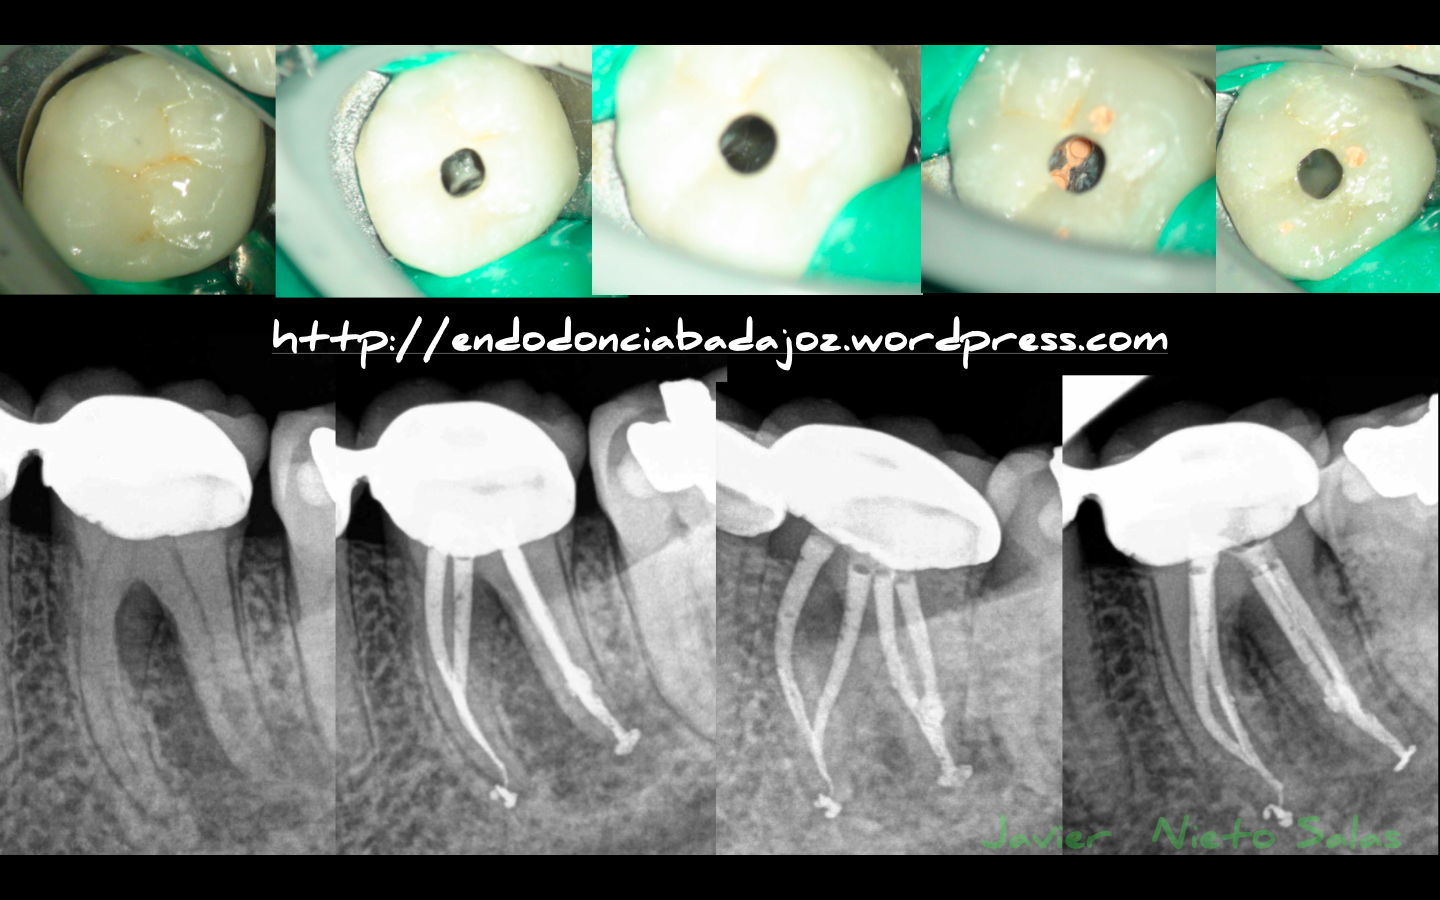

«La importancia de un buen diagnóstico va a determinar el pronóstico del caso». Cada vez son más los casos que nos encontramos con «fractura vertical». En estos dos casos que os ponemos, son tratamientos que nos envían para un retratamiento de conductos por fracaso del mismo. No sólo debemos valorar la imagen radiográfica, sino que debemos hacer un protocolo diagnóstico que nos ayudará a dar el verdadero problema.

La cirugía de diagnóstico es una alternativa para confirmar y verificar la situación.

1) Caso A: Motivo de fracaso, subobturación de los conductos mesiales. Vemos como corrigiendo el problema, es un tratamiento predecible

2) Caso B: Conductos omitidos y subobturación del conducto distal. Vemos la regeneración de la lesión a los 9 meses.